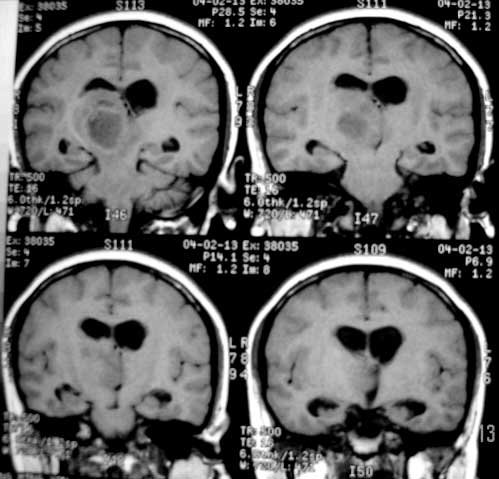

女性,28岁。头痛请会诊

右侧丘脑类圆形等t1,长t2病灶,t1增强明显强化。

女性,28岁。头痛请会诊。

考虑:①丘脑胶质瘤可能大。②脑积水。

t1等信号内出现点状高信号,考虑为出血灶,肿块内侧可见弧形低信号,为脑积液影。长t2,其内有混杂信号,周壁强化明显,内不规则强化,生长位置似在右侧丘脑,又似在来源于侧脑室,故脉络丛乳头状瘤不排外。

右侧丘脑胶质母细胞瘤可能

右侧丘脑胶质母细胞瘤?